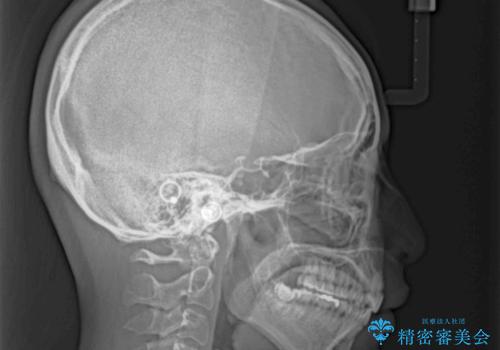

抜歯矯正を行ったことで、顎先のつっぱり感や口元の閉じにくさを解消することができました。